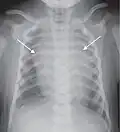

Different views (also known as projections) of the chest can be obtained by changing the relative orientation of the body and the direction of the x-ray beam. The most common views are posteroanterior, anteroposterior, and lateral. In a posteroanterior (PA) view, the x-ray source is positioned so that the x-ray beam enters through the posterior (back) aspect of the chest and exits out of the anterior (front) aspect, where the beam is detected. To obtain this view, the patient stands facing a flat surface behind which is an x-ray detector. A radiation source is positioned behind the patient at a standard distance (most often 6 feet, 1,8m), and the x-ray beam is fired toward the patient.

In anteroposterior (AP) views, the positions of the x-ray source and detector are reversed: the x-ray beam enters through the anterior aspect and exits through the posterior aspect of the chest. AP chest x-rays are harder to read than PA x-rays and are therefore generally reserved for situations where it is difficult for the patient to get an ordinary chest x-ray, such as when the patient is bedridden. In this situation, mobile X-ray equipment is used to obtain a lying down chest x-ray (known as a "supine film"). As a result, most supine films are also AP.

Typical views

Required projections can vary by country and hospital, although an erect posteroanterior (PA) projection is typically the first preference. If this is not possible, then an anteroposterior view will be taken. Further imaging depends on local protocols which is dependent on the hospital protocols, the availability of other imaging modalities and the preference of the image interpreter. In the UK, the standard chest radiography protocol is to take an erect posteroanterior view only and a lateral one only on request by a radiologist.[5] In the US, chest radiography includes a PA and Lateral with the patient standing or sitting up. Special projections include an AP in cases where the image needs to be obtained stat (immediately) and with a portable device, particularly when a patient cannot be safely positioned upright. Lateral decubitus may be used for visualization of air-fluid levels if an upright image cannot be obtained. Anteroposterior (AP) Axial Lordotic projects the clavicles above the lung fields, allowing better visualization of the apices (which is extremely useful when looking for evidence of primary tuberculosis).